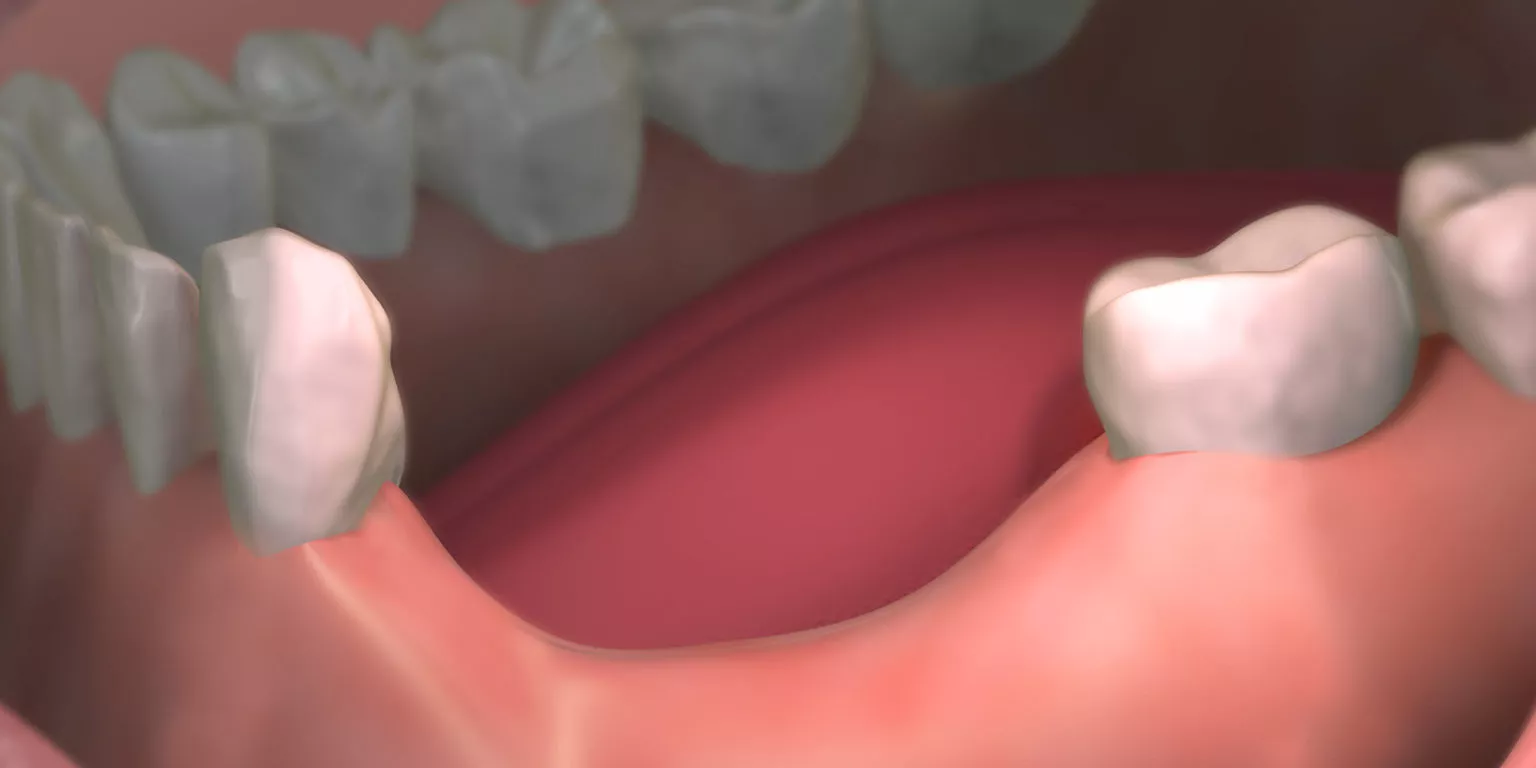

زراعة عظم الفك هي إجراء طبي يهدف إلى زيادة كثافة وسمك العظم في الفك لتحضير المنطقة لتركيب غرسات الأسنان بشكل آمن وثابت، تتم العملية باستخدام مواد عظمية طبيعية أو صناعية، وتساعد على تعزيز دعم الغرسات وتحقيق نتائج طويلة المدى.

تعتبر زراعة عظم الفك خطوة أساسية الأمر الذي يضمن نجاح عملية زراعة الأسنان، خصوصًا في الحالات التي تعاني من نقص العظم بسبب التسوس، أمراض اللثة، وفقدان الأسنان لفترات طويلة من أهميتها:

- تحافظ على شكل الفك الطبيعي وتمنع هبوط اللثة أو العظم.